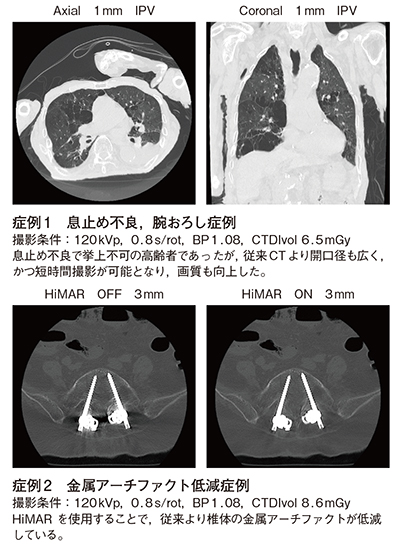

また,金属アーチファクト低減技術「HiMAR(High Quality Metal Artifact Reduction)」も実装されており,伊藤部長は「股関節に人工骨頭を留置している場合でも金属アーチファクトがしっかり抑制され,金属周囲の軟部組織も評価が可能です」と有用性を述べる。吉川技師長は,「HiMARは撮影後に適用できるため,必要に応じて再構成しています。脊椎にインプラントが埋め込まれた腰椎術後の症例でも,アーチファクトを低減した画像を得ることができ,MPRや3D画像の作成が容易です」と,画像処理においてもメリットが大きいと話す。

Supria Opticaによる臨床画像